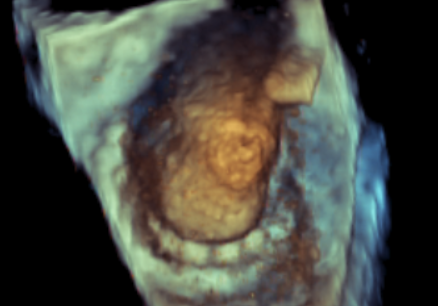

术中影像监护与评估(DSA&TEE)

原生物瓣少量反流

过瓣流增快,呈“五彩状”